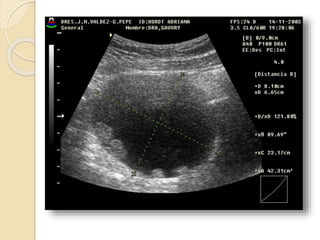

Poliquistosis Ovárica:

Se describe este síndrome como cambios

escleroquísticos en el ovario, mas

amenorrea, infertilidad e hirsutismo.

Ecográficamente vamos a ver

agrandamiento de ambos ovarios con

quistes subcorticales de menos de 1cm.,

mas incremento de las dimensiones del

estroma y fibrosis subcapsular.